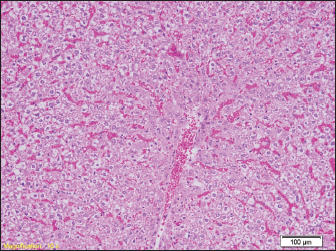

In the liver samples of all groups of rats, relatively uniform changes are observed, which in each sample include a certain degree of congestion, with overcrowding of the centrolobular veins, but also the veins of the portal spaces, as well as the dilation of the sinusoids filled with erythrocytes, while the hepatocytes in places show signs of fluffy degeneration (Figs. 5 and 6.)

Fig. 5. Blood filling of hepatic sinusoids and centrolobular vein (HE, ×100).

Fig. 6. Congested portal blood vessels as well as sinusoids, and hepatocytes with balloon appearance in places (HE, ×200).

However, studies have shown that there are statistical differences in the number of diatoms in false positive cases and actual drowning cases. Therefore, a comprehensive analysis of multiple organs, rather than just one organ, would be more useful for the diagnosis of drowning. Relatively uniform changes are observed in the liver samples of all groups of rats, which in each sample include a certain degree of congestion, with overcrowding of the centrolobular veins, but also the veins of the portal space, as well as dilation of sinusoids-filled with erythrocytes, while hepatocytes in places show signs of paper degeneration.